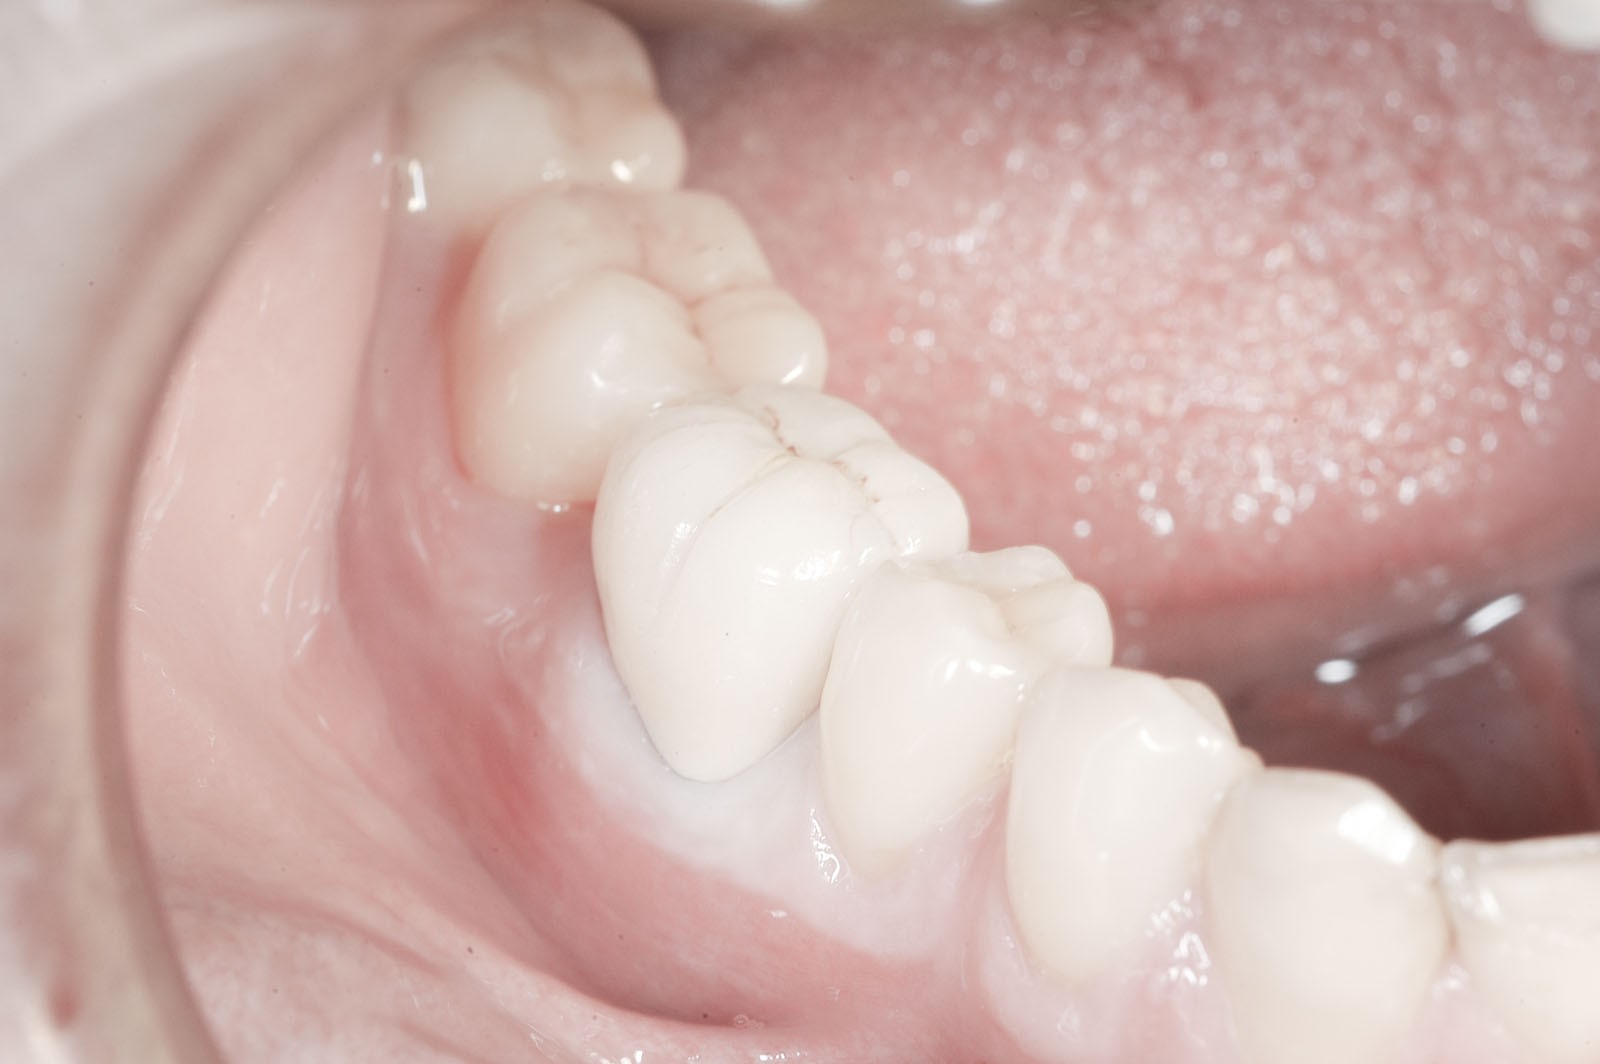

Korona to uzupełnienie protetyczne odtwarzające prawidłowy kształt, funkcję i estetykę uszkodzonego zęba. Klasyfikowana jest jako uzupełnienie stałe, czyli niewyjmowane z jamy ustnej, ze względu na to, że cementuje się ją na oszlifowanym filarze. Może być wykonana z czystej ceramiki lub z ceramiki na podbudowie metalowej lub z tlenku cyrkonu. Tak wykonuje się ostateczne korony ze względu na walory estetyczne i trwałość materiału. Tymczasowe korony ochronne można wykonać z materiału kompozytowego lub akrylu.

Komfortową alternatywą dla mostu jest rehabilitacja implanto-protetyczna, zarówno w przypadku braku pojedynczego, jak i większej liczby zębów. Implantacja wskazana jest w szczególności, gdy zęby sąsiadujące z luką są zdrowe, nie leczone kanałowo, a podłoże kostne spełnia warunki dla implantacji. Pozwala to uniknąć szlifowania zębów filarowych stojących obok luki, a przyszła konstrukcja protetyczna najczęściej nie uwzględnia przęsła mostu, które może sprawiać trudności w utrzymaniu higieny jamy ustnej. Korony i mosty wsparte na implantach przenoszą siły powstające w procesie żucia przez osie implantów wszczepionych w kość. Tworzy to układ działania sił najbardziej zbliżony do fizjologicznych warunków jamy ustnej z uzębieniem. Jest on optymalny dla zdrowia i zachowania tkanki kostnej. W ten sposób przenoszona siła powoduje wzmocnienie kości, nie zaś jej resorpcję, czyli zanik.